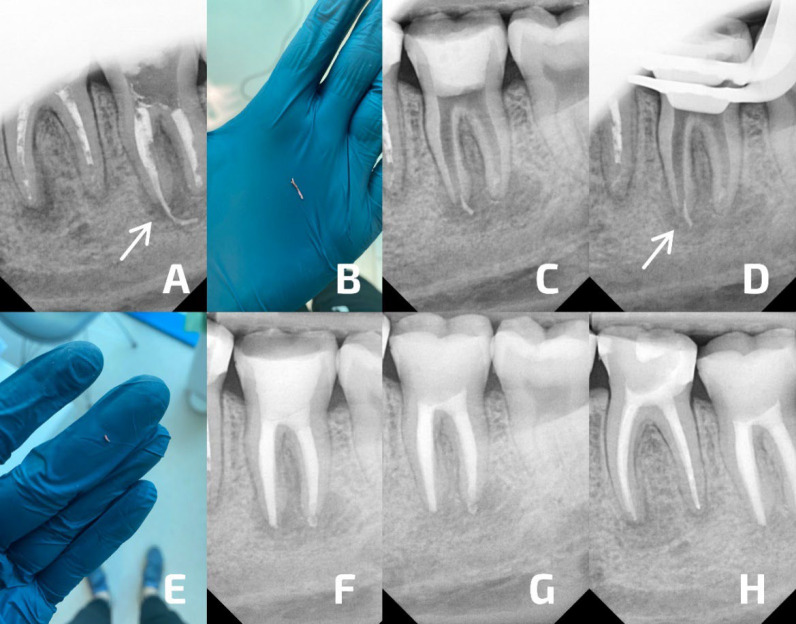

Continuous improvement and technological progress in the field of microscopic endodontics enable a gradual increase in indications for non-surgical root canal treatment. While most publications report successful surgical management of overfill or extruded foreign bodies into the periapical area, very few report that this complication can be successfully managed with non-surgical endodontic treatment. This case report presents successful management of a lower left second molar (tooth #37) diagnosed with exacerbated chronic apical periodontitis and massive overfill in a 36-year-old patient WITH non-surgical endodontic treatment AND bent H-file to remove extruded material under dental operating microscope control. It discusses technical aspects of this procedure, as well as its possible complications, including a sodium hypochlorite accident.